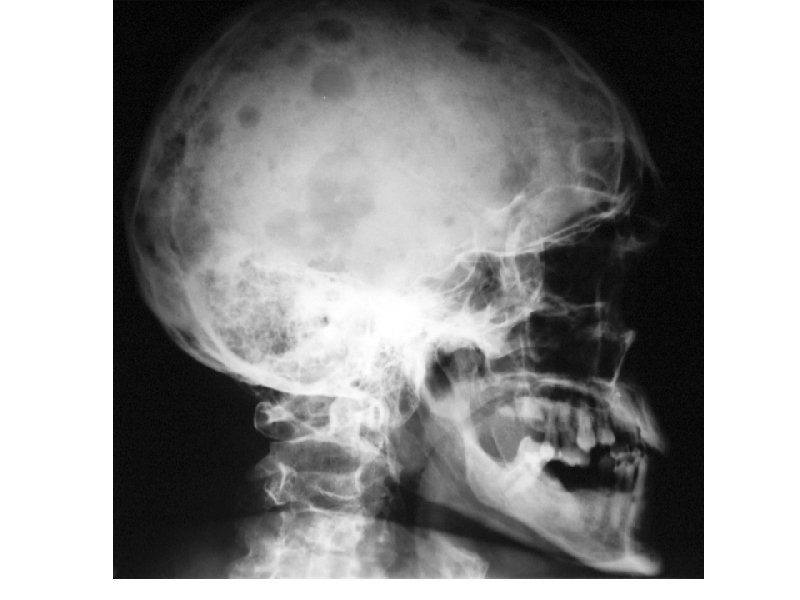

Клинические проявления ММ • Множественные остеолитические очаги Поражение костей повреждения плоских костей и эпифизов трубчатых костей • Диффузный остеопороз (остеопения) • Костные переломы • Уменьшение роста (вертебральный коллапс) Эффекты, ассоциированные с остеодеструкцией Внекостные плазмацитомы • Болевой синдром у 20 -40% Гиперкальциемия ( утомляемость, жажда, тошнота, запоры, повреждение почек, полиурия, сонливость, судороги, кома) • Гиперкальцийурия • Вовлечение мягких тканей преимущественно в области головы/шеи, очаги в печени, почках,

А- рентгенограмма, В- мультидетекторная КТ (МДКТ), Смагнитнорезонансная томография (МРТ)

А-ренгенограмма, В-МДКТ